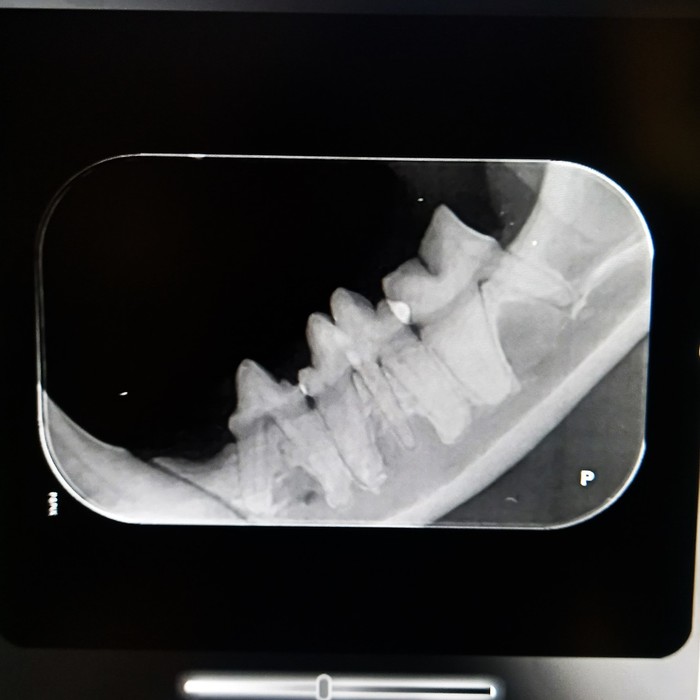

Rentgeny zubů se využívají na zobrazení hlubších vrstev zubů, kořenového systému zubů, posouzení parodontu a čelistních kostní.

Korunka zubu: přítomnost a celistvost skloviny, šířka dentinu a jeho případné patologie, šířka dřeňové dutiny, celistvost zubu, při frakturách rozsah zlomenin, hledáme resorptivní léze, kazy, částečné/úplné fraktury, změny tvaru a celistvosti korunky

Krček zubu: celistvost krčku, resorptivní léze, kazy, fraktury

Kořen zubu: posouzení cementu na povrchu zubů, dentinu, dřeňové dutiny, fraktur kořenů, tvaru kořenů a jeho případných výběžků, přítomnosti tzv. pulpálních kamenů, osteoresorptivních lézí

Čelist: posouzení případných periapikálních reakcí, přítomnosti, úbytku či změny struktury alveolární kosti, přítomnost zlomenin čelisti či nádorového procesu, ne/přítomnost některých zubů

kořenové anomálie

kořeny mléčných zubů

periapikální absces

polámané kořeny v čelisti

vstřebávající se kořen špičáku

resorptivní léze